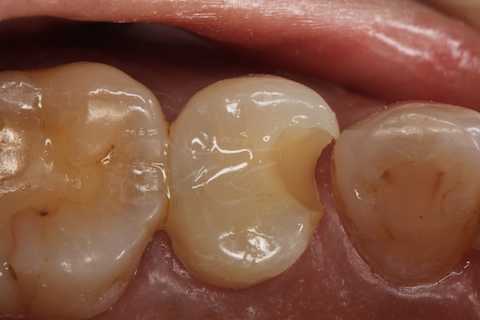

40代女性、左上5、冷水痛+

今回この方は5本のCR充填を一挙に行ったので、かなり疲れた。

注意点はCRの接着面は新鮮歯質を確保して歯髄に近いところの軟化象牙質はあまり追求しないでも良い。α-TCPセメントの硬化と接着を妨げない程度に乾燥できれば良い。軟化象牙質は原材料のα-TCPと多少の水分があれば自然に再硬化するようだ。

この症例はストリップスを使っていない。使わない方が確実に充填できると思う。

では時系列でどうぞ